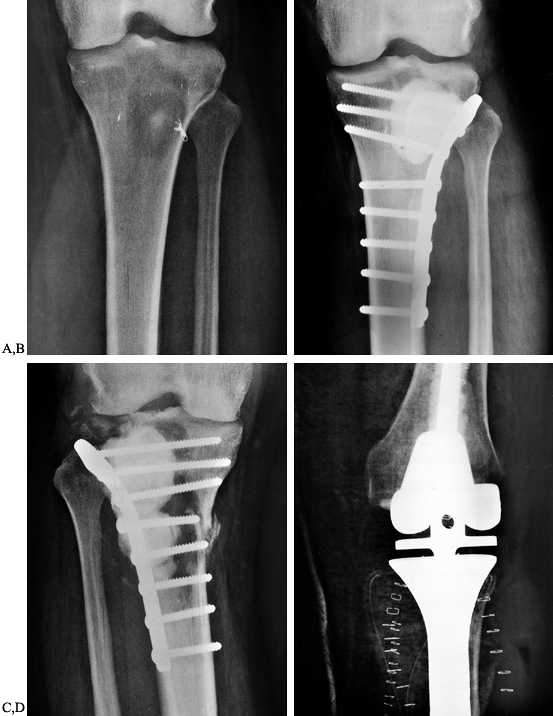

femur and proximal tibia are usually managed by curettage of the

lesion, cement augmentation, and plate fixation (Fig. 130.4).

It is more difficult to achieve rigid fixation with intramedullary rods

when the lesion approaches the articular surface. For the distal femur

we use a dynamic compression screw, whereas in the tibia we use lateral

tibia plateau plates or medial buttress plates, depending on the

location of the bone destruction. We avoid removing intact cortical

bone and generally do the exposure and plate fixation on the side of

the greatest bone destruction.

![]() |

|

Figure 130.4. A: Anteroposterior radiograph of the tibia showing a destructive lesion in a patient with renal cell carcinoma. B: Anteroposterior radiograph of the tibia following curettage and methyl methacrylate augmentation and plate fixation. C:

Anteroposterior radiograph of the tibia showing progressive bone destruction following two courses of external beam irradiation and plate fixation with cement augmentation. D: Anteroposterior radiograph demonstrating resection of the proximal tibia and reconstruction with a custom modular knee replacement. |